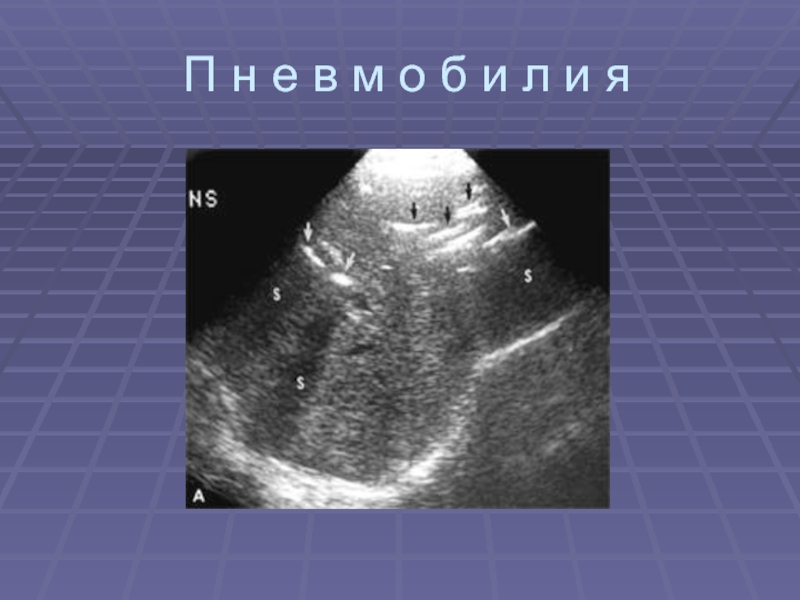

Пневмобилия – цепочки гиперэхогенных структур с эффектом реверберации

в проекции внутрипеченочных протоков и часто во внепеченочных протоках; кишечное содержимое (в виде гиперэхогенных тяжей) при больших размерах фистулы

Дифдиагноз с пневмобилией при анаэробном холангите, при недостаточности сфинктера Одди, после проведения ЭРПХГ, после реконструктивных вмешательствах